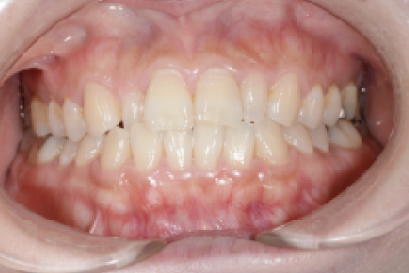

• 症例4

術前

*

術後

年代、性別

20代、男性

職業

学生

主訴

歯並び相談

部位

抜歯を併用してのインビザラインによる全顎矯正

治療期間

1年6ヶ月

矯正費用

95万円

施術説明

他院の矯正専門医院でマウスピース矯正は不可能と言われて、セカンドオピニオンで来院されました。就職活動が始まるまでに、歯並びを治療しておきたいということでしたが、当院の矯正専門医であるインビザライン・ファカルティーの山本先生による検査では、インビザラインで治療が可能と診断されました。抜歯を伴う矯正は通常長期にわたる事が多いですが、1年半で治療も完了し非常に喜んでもらえました。

副作用・リスク

なし